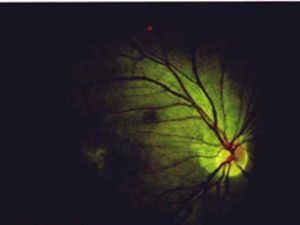

视直如曲,中医病名。是指眼外观如常,而自视正直之物若弯曲状或视物扭曲变形的内障眼病。本病好发于成年人,以老年偏多,单眼、双眼或双眼先后发病。饮食不节,情志内伤,劳倦过度常易罹患。本病运用中医辨证与辨病结合的优势治疗,预后较好;不治或治疗不当,则预后差,甚者可遗留永久性视力障碍,本病类似于西医学的中心性浆液性视网膜脉络膜病变。

均为视物形态变异之病证,其临床表现不相同,视正反斜全身证候偏重。在眼部的表现视正反斜即眼所注视物体形态结构正常,仅由正位变为歪斜状;视直如曲是注视之物体形态结构有变,“弓弦界尺视之皆如钩”,即视直线有钩,视正直物扭曲,其病变部位在眼内视衣黄斑部,有渗出、出血、瘢痕等改变。